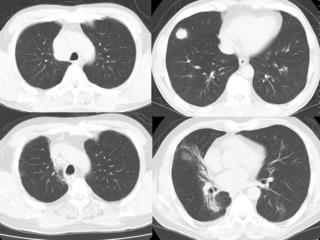

CTで見ると…

3Dだと、こうなります。

気管狭窄ですね。こういう所見もレントゲンで捉えることができるのです。